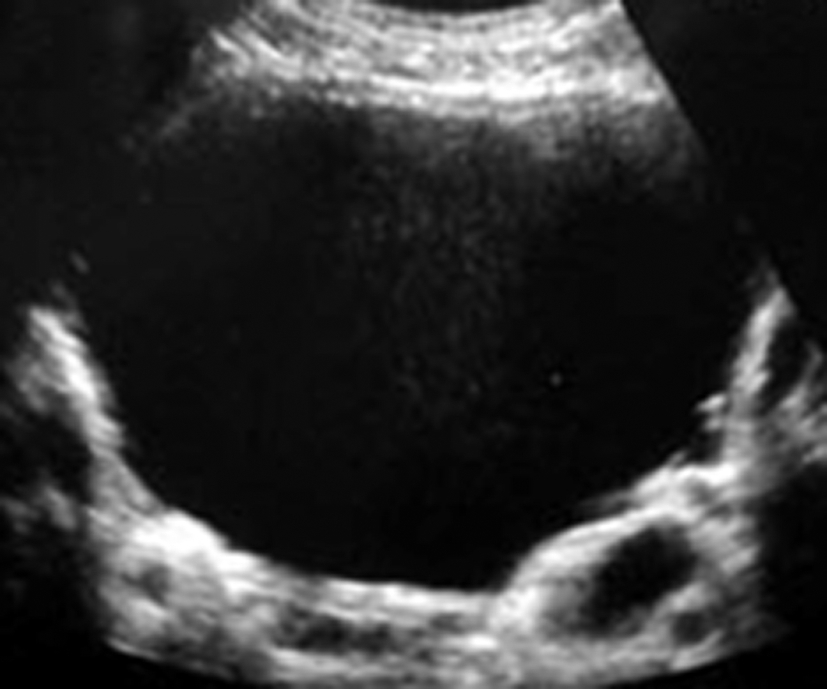

Que voit-on sur cette échographie?

kyste du rein= d’allure simple car lésion anéchogène avec renforcement postérieur non vasculaire sans végétations et à parois fines. (! Bosniak= définition scannographique!)